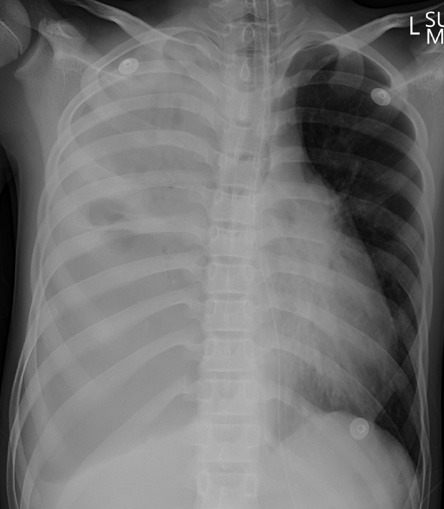

A 13-year-old male with a history of daily e-cigarette use and no prior medical illness presented to our hospital with a one-month history of intermittent cough and fever, along with worsening dyspnea over the past day. He denied any episodes of hemoptysis. Upon physical examination, his blood pressure was 152/82 mmHg, respiratory rate was 35 breaths/min, heart rate reached 150 beats/min, and oxygen saturation was 89% on room air. Lung auscultation revealed reduced air entry over the right lung, while the corresponding chest radiograph noted a right-sided pleural effusion [Figure 1]. Blood investigations revealed leukocytosis of 19.53 × 103/uL (reference range: 4–11× 103/uL) and a C-reactive protein level of 213.4 mg/L (reference range: < 5.0 mg/L). Renal function, liver function, and glucose investigations were all within the normal range. An arterial blood gas analysis, performed while the patient was on a rebreather face mask with a flow rate of 15 L/min, indicated decompensated metabolic acidosis with hyperlactatemia (pH 7.25, pO2 249 mmHg, pCO2 30 mmHg, HCO3- 13.2 mmol/L, and lactate 8.2 mmol/L). Due to worsening respiratory distress, the patient was subsequently intubated and transferred to the high-dependency unit.

Figure 1: Chest X-Ray on 2 August 2022. The frontal chest radiograph shows complete opacification of the right hemithorax, with evident mass effect resulting in tracheal and mediastinal deviation to the left. The left lung field appears clear.